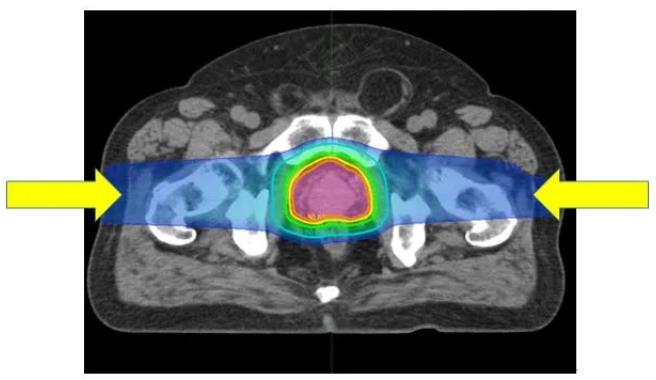

(图)质子治疗前列腺癌:从左右两个方向进行照射可提供集中在前列腺上的良好剂量分布。